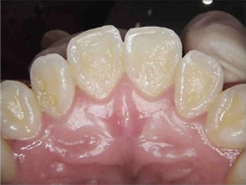

症例(Before・After)

術前

エアフローによるクリーニング

| 治療内容 |

専用パウダーと水のスプレーを噴射し、歯面や歯周ポケット内のバイオフィルム(細菌の膜)および着色汚れを除去。

|

| 期間 |

1回(30~45分)

| 費用 |

4, 400円(自由診療/着色除去) ※バイオフィルム除去のみの場合は2,200円

| 注意事項(リスク等) |

施術中、水流やパウダーにより痛みや違和感を感じる場合があります。